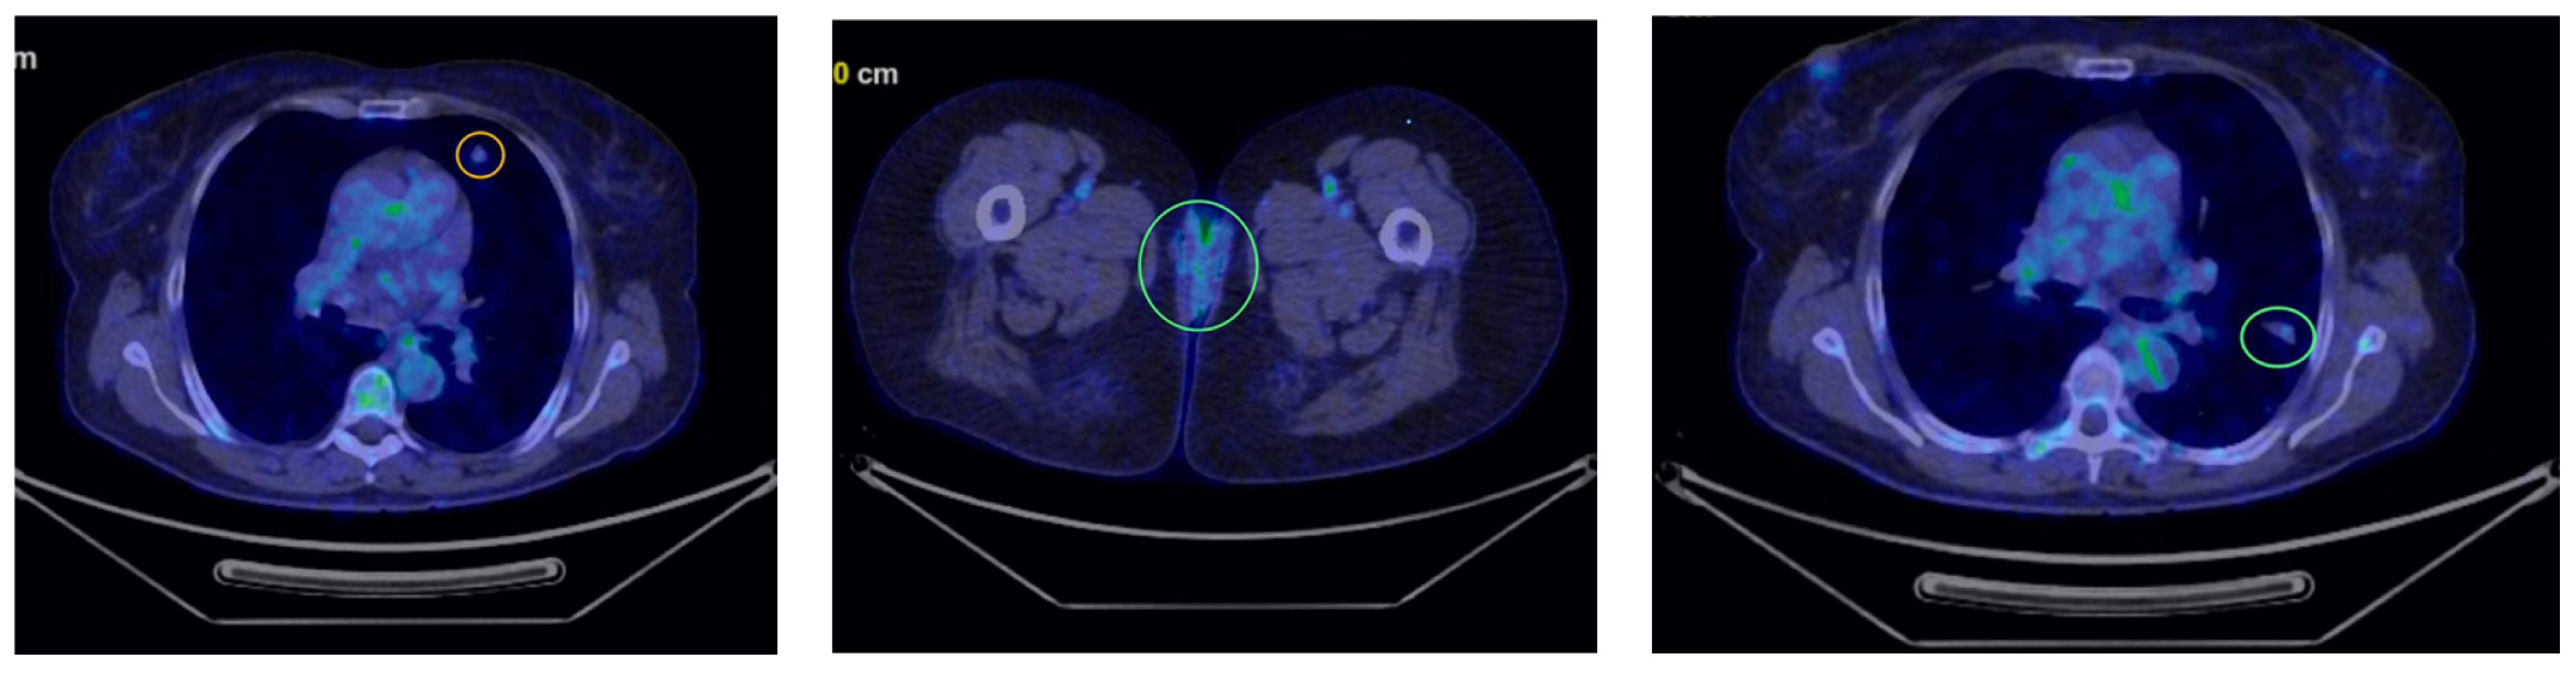

Five month later, the patient underwent her first follow-up PET-CT, which revealed multiple bilateral non-calcified pulmonary nodules, most of which showed minimal uptake, raising suspicion of secondary metastases (Figure 2). In the follow-up PET-CT performed six months later, multiple non-calcified nodules were observed bilaterally in the pulmonary parenchyma, with progressive dimensional and metabolic increases, the largest measuring 28/20 mm. These nodules were biopsied. The preliminary histopathological examination suggested carcinomatous infiltration, which was confirmed by the final histopathological report as clear cell carcinoma with pulmonary localization, indicative of secondary metastasis (Figure 3).

Figure 2.

First PET-CT revealing multiple bilateral non-calcified pulmonary nodules (marked in yellow and green circles).